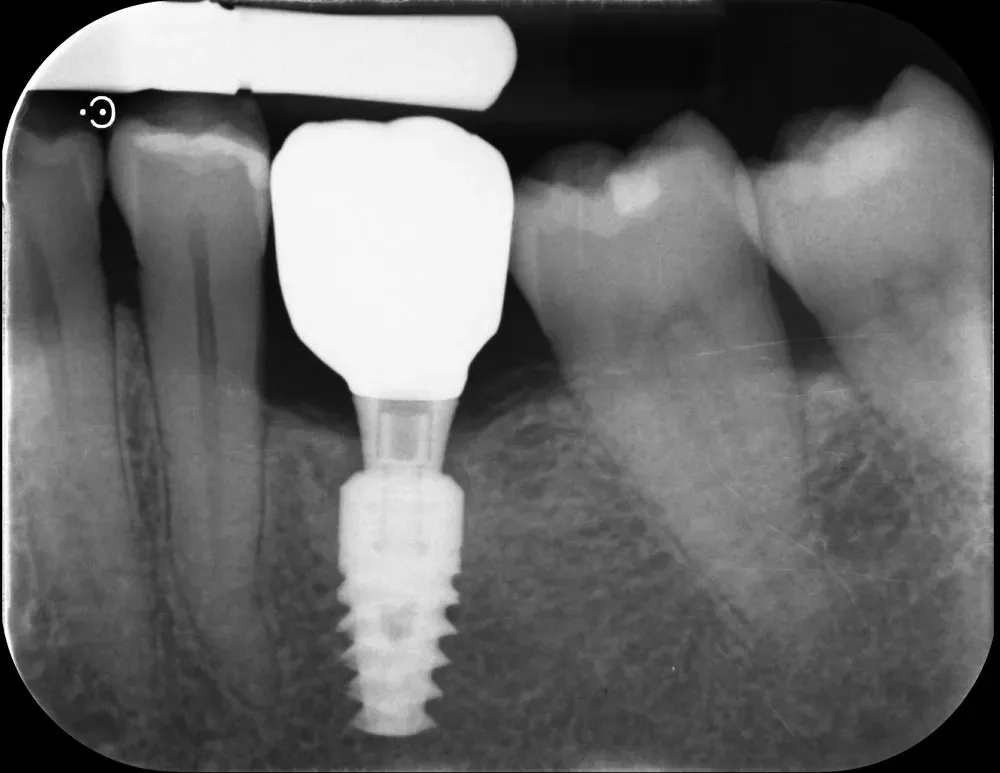

Gli impianti transmucosi devono essere posizionati transmucosi, soprattutto se hanno connessioni non particolarmente “sigillanti”. Usati in tal guisa, sono perfetti. Le immagini che seguono dimostrano che i transmucosi, se posizionati al giusto livello verticale, causano ZERO riassorbimento della cresta ossea.

Sull’altezza: la review di Muñoz e collaboratori (https://doi.org/10.1111/clr.14025), basata solo su RCT, ha identificato una soglia di 2 mm. Abutment alti almeno 2 mm svolgono un ruolo protettivo contro la perdita ossea marginale, permettendo la formazione dell’adesione mucosale sovracrestale. Questo effetto appare indipendente dallo spessore dei tessuti molli, anche se in caso di tessuti sottili è importante posizionare gli impianti sottocrestali (o meglio, “infracrestali”) per consentire la formazione del complesso mucosale sovracrestale.

La regola dei 4mm di Linkevičius ci viene in aiuto per stabilire la posizione verticale che protegge l’impianto dal riassorbimento osseo, sempre nel caso di connessioni affidabili dal punto di vista batteriologico. Nelle prossime immagini, dei monconi protesici relativamente lunghi su impianti a connessione conica, testimoniano l’ottimo risultato reale di questo concetto, con impianti perfettamente integrati e privi di infiltrazione infiammatoria, anche in condizioni ossee impegnative.